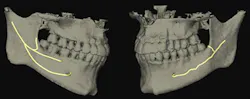

As the inferior alveolar nerve (IAN) approaches the mental foramen, the canal turns upward on the buccal side of the mandible.

The IAN emerges from the mental foramen and generates the mental nerve. The mental portion of the IAC can course straight, vertical, or in an anterior loop fashion. In the anterior loop, the nerve runs upward and courses toward mid-mandible before looping and heading back toward the mental foramen (figure 1).

The literature1 has reported variations in the prevalence of the anterior loop from 7%–88%, with a mean prevalence of around 28%.2 Trauma to this region (mandibular premolar-incisor) can induce sensory disturbances, increased bleeding, and pain post-implant therapy in a region otherwise known as a “safe area.”

Taking a high-quality CBCT image may help with neural imaging and deciphering if an anterior loop is present.